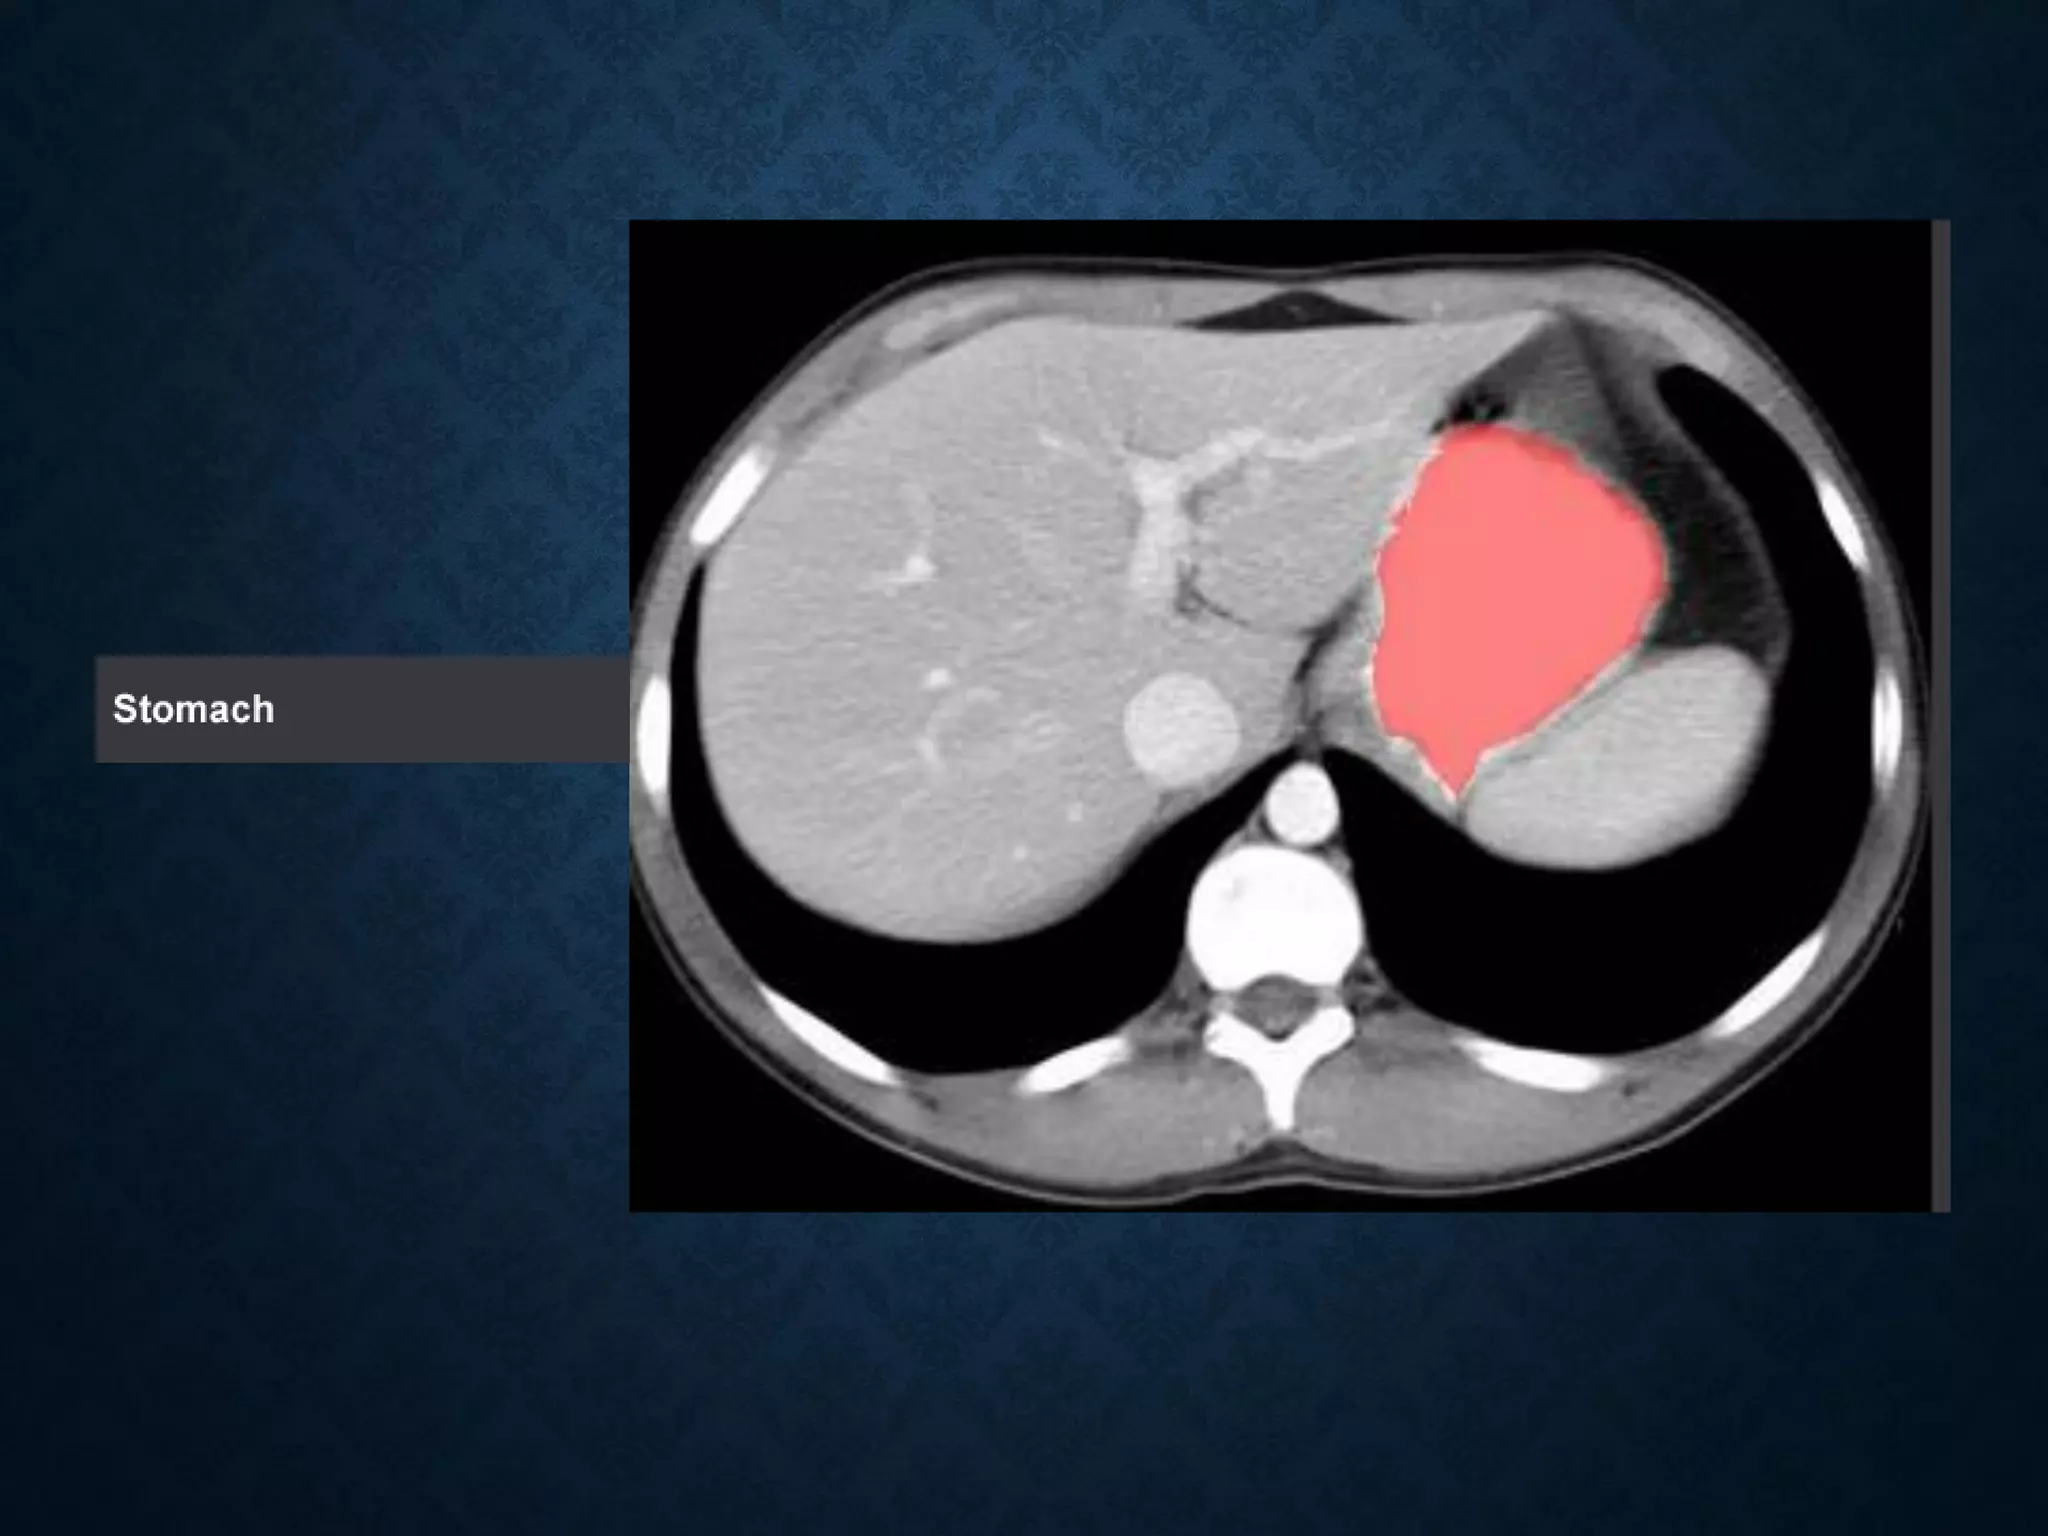

STOMACH

Identify the followingstructures in the body CT to the right. To view the location of the structure in the image click on the label at the left and the structure will be indicated in the image. Abdominal CT scans typically begin just above the diaphragm, so the first slice you see is of the lower chest.